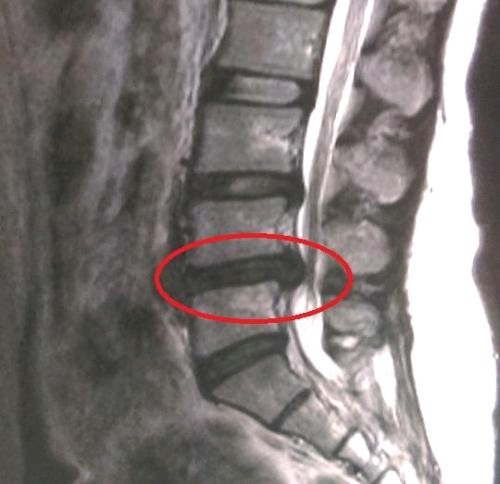

腰椎间盘突出症 是指椎间盘向椎管方向突出神经受压迫进而引发出的一系列症状的疾病。典型症状有:腰痛、下肢的疼痛麻木等。

图片发自160医生App

对于腰椎间盘突出或膨出,避免久站和久坐,小燕飞可以锻炼腰背部肌肉力量,从而改善症状。